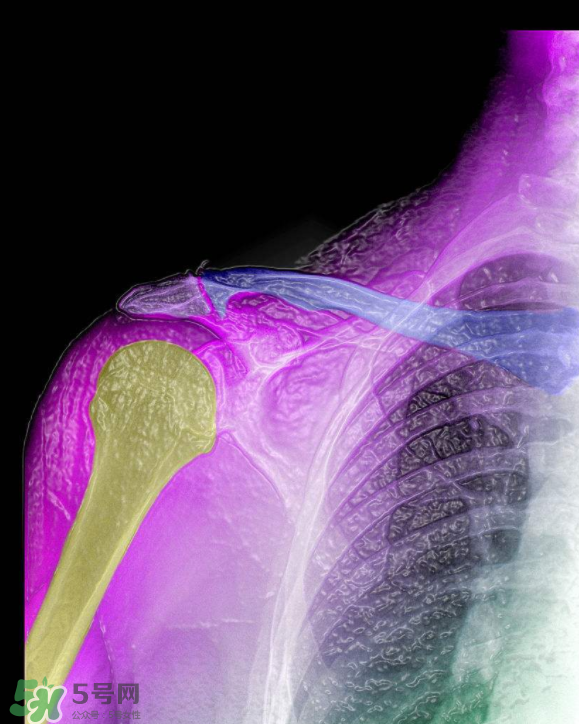

骨刺是怎么形成的?骨刺怎么治療?

骨刺是一種比較發(fā)作起來會(huì)讓人很難受的病,很多人不清楚骨刺到底是什么樣的,下面5號(hào)網(wǎng)的小編為你們介紹骨刺是怎么形成的?骨刺怎么治療?

1、骨刺,多發(fā)于活動(dòng)度最大、負(fù)重最多的頸椎、腰椎、骶椎、膝關(guān)節(jié)、足跟等部位。隨著年齡的增長(zhǎng),人的關(guān)節(jié)軟骨彈性會(huì)銳減,軟骨膠原纖維顯露,關(guān)節(jié)中部活動(dòng)時(shí)極易磨損,其外周軟骨面便代謝性增殞肥厚,最后骨化形成骨刺。職業(yè)性持久用力、長(zhǎng)期被迫體位不良、慢性或機(jī)械性刺激、跌打損傷等是誘發(fā)骨刺形成的原因。

2、骨刺患者一旦增生的骨刺刺激鄰近組織和壓迫神經(jīng)根時(shí),就會(huì)出現(xiàn)局部或放射性骨刺的疼痛。主要表現(xiàn)為上肢麻痹、肩背疼痛、頸項(xiàng)僵硬、頭暈、胸悶不舒、心悸心慌、坐骨神經(jīng)痛、下肢麻痹痛、怕冷、膝關(guān)節(jié)腫痛、上下樓梯困難、不能下蹲等一系列骨刺的病理變化。如不及時(shí)治療,就會(huì)使骨刺的病情加重,增加治療難度。因此,這些都是骨刺形成的原因。